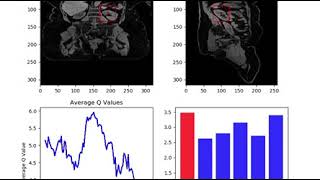

Rapid Cardiac MR Using Highly Accelerated Deep-Learning Reconstructed Cine Landmark Detection in a 3D MR Image using Deep Reinforcement Learning

Landmark Detection in a 3D MR Image using Deep Reinforcement Learning Detect any Landmarks or heritages with CNN